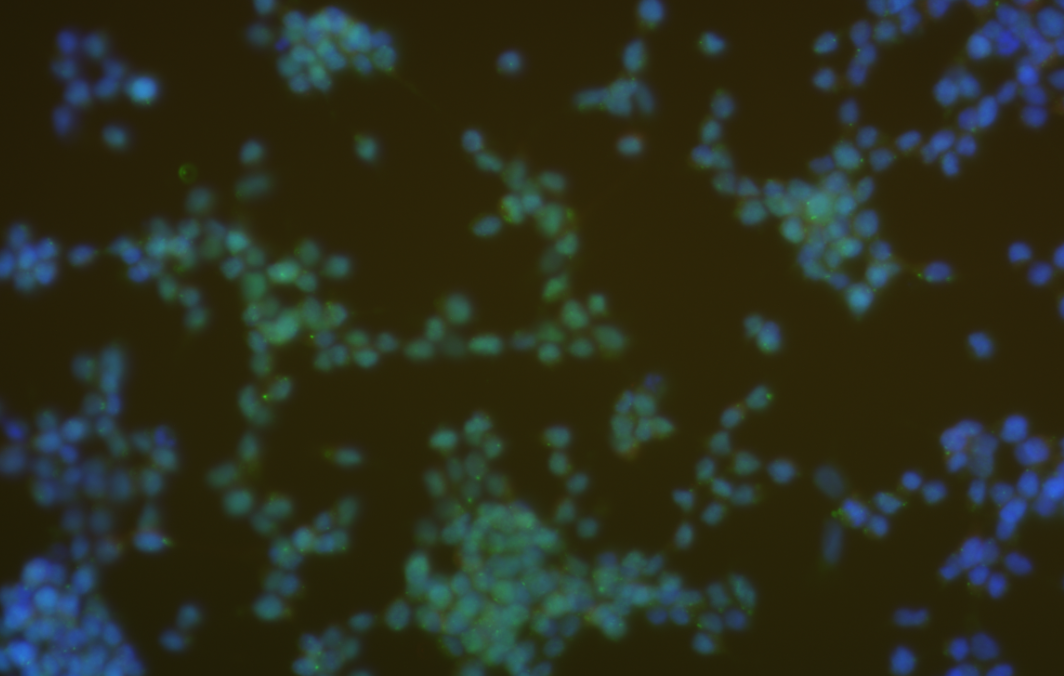

免疫熒光是一種利用抗原-抗體反應進行細胞或組織中抗原物質定位的技術。它利用熒光染料標記抗體,使其與特定的抗原結合,然后通過熒光顯微鏡觀察和分析熒光信號。免疫熒光主要用于研究細胞的結構和功能、檢測生物分子間的相互作用以及疾病診斷等。

免疫熒光的觀察和分析主要通過熒光顯微鏡進行,可以觀察熒光的顏色、亮度、分布等信息,從而對細胞或組織的結構和功能進行分析。